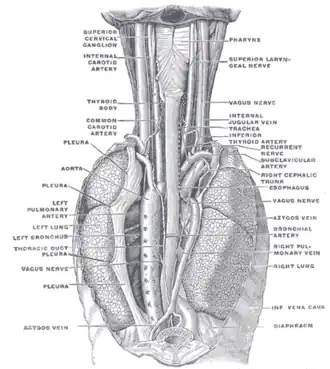

Plan of the upper portions of the glossopharyngeal, vagus, and accessory nerves. | |

Course and distribution of the glossopharyngeal, vagus, and accessory nerves. | |

Upon leaving the medulla oblongata between the olive and the inferior cerebellar peduncle, the vagus nerve extends through the jugular foramen, then passes into the carotid sheath between the internal carotid artery and the internal jugular vein down to the neck, chest, and abdomen, where it contributes to the innervation of the viscera, reaching all the way to the colon. Besides giving some output to various organs, the vagus nerve comprises between 80% and 90% of afferent nerve fibers conveying sensory information about the state of the body's organs to the central nervous system.[4]

The right and left vagus nerves descend from the cranial vault through the jugular foramina,[5] penetrating the carotid sheath between the internal and external carotid arteries, then passing posterolateral to the common carotid artery. The cell bodies of visceral afferent fibers of the vagus nerve are located bilaterally in the inferior ganglion of the vagus nerve (nodose ganglia).The vagus runs parallel to the common carotid artery and internal jugular vein inside the carotid sheath.

Right Vagus Nerve: The right vagus nerve gives rise to the right recurrent laryngeal nerve, which hooks around the right subclavian artery and ascends into the neck between the trachea and esophagus. The right vagus then crosses anterior to the right subclavian artery, runs posterior to the superior vena cava, descends posterior to the right main bronchus, and contributes to cardiac, pulmonary, and esophageal plexuses. It forms the posterior vagal trunk at the lower part of the esophagus and passes through the diaphragm to enter the abdomen through the esophageal hiatus.

Left Vagus Nerve: The left vagus nerve enters the thorax between left common carotid artery and left subclavian artery and descends on the aortic arch. It gives rise to the left recurrent laryngeal nerve, which hooks around the aortic arch to the left of the ligamentum arteriosum and ascends between the trachea and esophagus. The left vagus further gives off thoracic cardiac branches, breaks up into the pulmonary plexus, continues into the esophageal plexus, and enters the abdomen as the anterior vagal trunk by way of the esophageal hiatus of the diaphragm.

The position and relation of the esophagus in the cervical region and in the posterior mediastinum, seen from behind

The position and relation of the esophagus in the cervical region and in the posterior mediastinum, seen from behind -